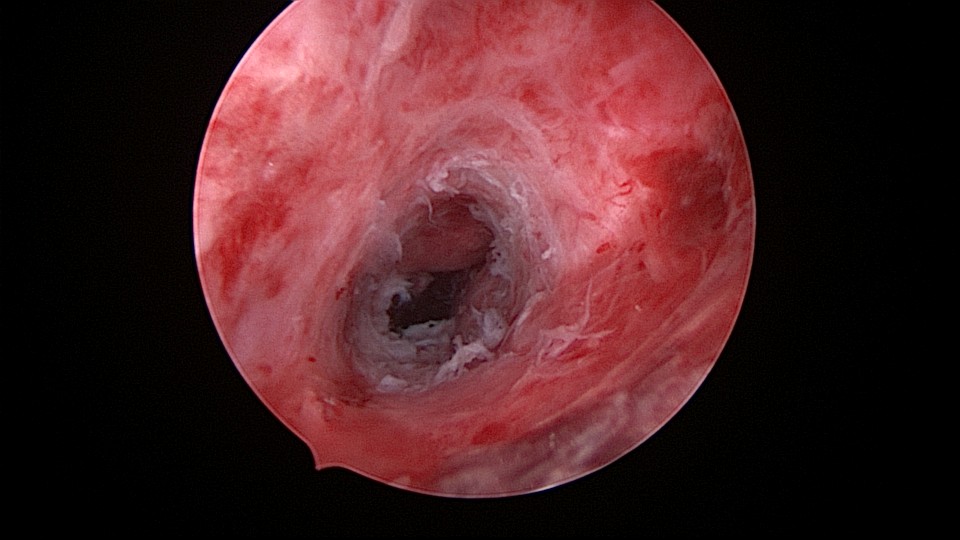

患者54岁,G2P1,顺产1次。安环26年,绝经1年,外院取环失败,子宫穿孔。宫腔镜术前B超提示子宫前位,盆腔未见异常。子宫极度前倾前屈位,宫腔下段后壁偏右穿孔,宫腔镜进入盆腔,见肠脂垂,未见积血,宫腔镜退出盆腔,寻找节育环。手术大部分时间在寻找宫颈内口和宫腔方向,在子宫穿孔的左上方找到宫颈内口,宫腔镜艰难进入宫腔,异物钳取环就迎刃而解了,取出一枚O型环。